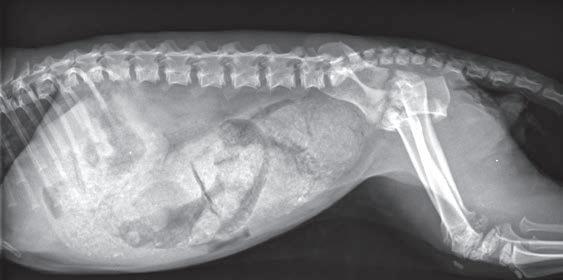

Issuu converts static files into: digital portfolios, online yearbooks, online catalogs, digital photo albums and more. Sign up and create your flipbook.